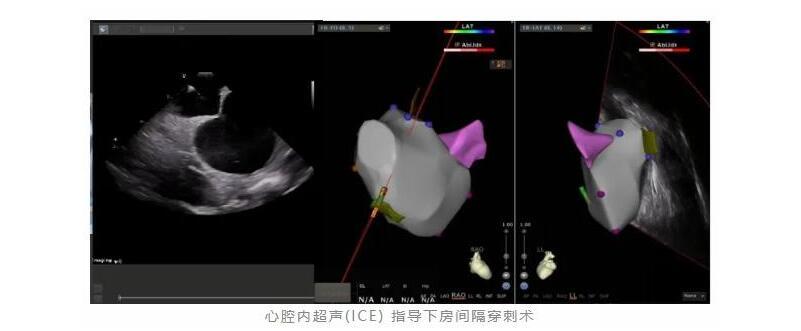

近日,哈医大四院心内五病房肖模超教授电生理团队再次实现技术突破,成功完成一例心腔内超声(ICE)指导下零造影剂的绿色房颤射频消融术。该术式不仅安全有效,而且摆脱了对造影剂及射线的依赖,为一些特殊人群(如孕妇、合并严重肾功能不全、造影剂过敏等)带来希望。

患者杨先生为中老年男性,间断发作心悸,口服药物治疗效果欠佳,手术意愿强烈,有房颤射频消融术的适应症。由于房颤射频消融术中需行房间隔穿刺,以构建从股静脉至左房的导管径路。常规房间隔穿刺需在X线指引下完成,注入造影剂明确穿刺部位、左房及肺静脉形态。患者既往行冠脉造影术后出现严重造影剂过敏,周身红肿、甚至出现过敏性休克,利用大剂量激素才得以缓解。回想起当时的经历杨先生仍心有余悸,对射频消融术中应用造影剂十分畏惧。肖模超教授电生理团队经过术前讨论,充分评估患者病情,认为可以采用无造影剂策略,通过心腔内超声(ICE)指导房颤射频消融术,避免再次造影剂过敏。

ICE(intracardiac echocardiography)即心腔内超声技术。与传统体外超声诊断技术不同,心腔内超声技术是将一根圆珠笔芯粗细的超声导管,通过外周血管置于心腔内,利用位于导管头端的超声探头,近距离、实时精准获取心脏解剖结构,并可以同步显示心脏血流动力学,实时动态评估局部心肌和整体心脏功能。近年来,在心脏介入治疗和电生理检查中,显示出良好的应用前景。心腔内超声就像医生安在心脏内的一双眼睛,医生可以通过超声图像“直视”心脏结构,并结合三维解剖标测系统构建出心脏模型,更快更好更安全地完成心脏手术。ICE具有操作灵活、精准安全、无需全身麻醉、无食管损伤、无需使用造影剂和显著减少X线暴露时间等优点,在房颤消融手术中主要应用于探查心腔内血栓、引导房间隔穿刺、精准定位消融导管及监测术中并发症等方面,大大优化了手术流程、提高了手术安全性。

据肖模超教授介绍,ICE引导下的射频消融术,为无法使用或耐受经食道超声(如患有食管疾病)、造影剂过敏以及有严重畸形或心脏转位的房颤患者提供了新的解决方案,让更多的房颤患者远离卒中危害,提高了生活质量。另外,传统的射频消融技术,医生需要利用X线和三维标测系统等技术进行“定位”,使用ICE技术极大地减少了X线的用量,甚至可以实现零射线,对患者和医生而言都更加安全、绿色。